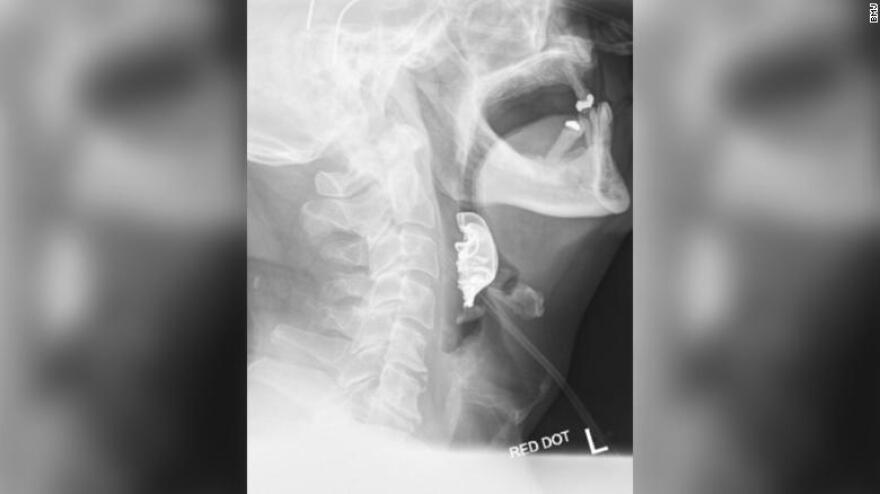

Τελικά, μέσω μιας διαγνωστικής διαδικασίας οι γιατροί εντόπισαν το ημικυκλικό αντικείμενο σφηνωμένο πάνω στις φωνητικές χορδές του άνδρα, που είχε προκαλέσει εσωτερικές φουσκάλες και πρήξιμο.

Ο 72χρονος, που είχε χάσει την μερική οδοντοστοιχία κατά την πρώτη του επίσκεψη στο νοσοκομείο αλλά δεν είχε φανταστεί ότι αυτή βρισκόταν στον... λαιμό του, εισήχθη εσπευσμένα στο χειρουργείο για την αφαίρεση της μερικής οδοντοστοιχίας, που αποτελούνταν από το μεταλλικό πλαίσιο που εφαρμόζει στην οροφή του στόματος και τρία τεχνητά δόντια.